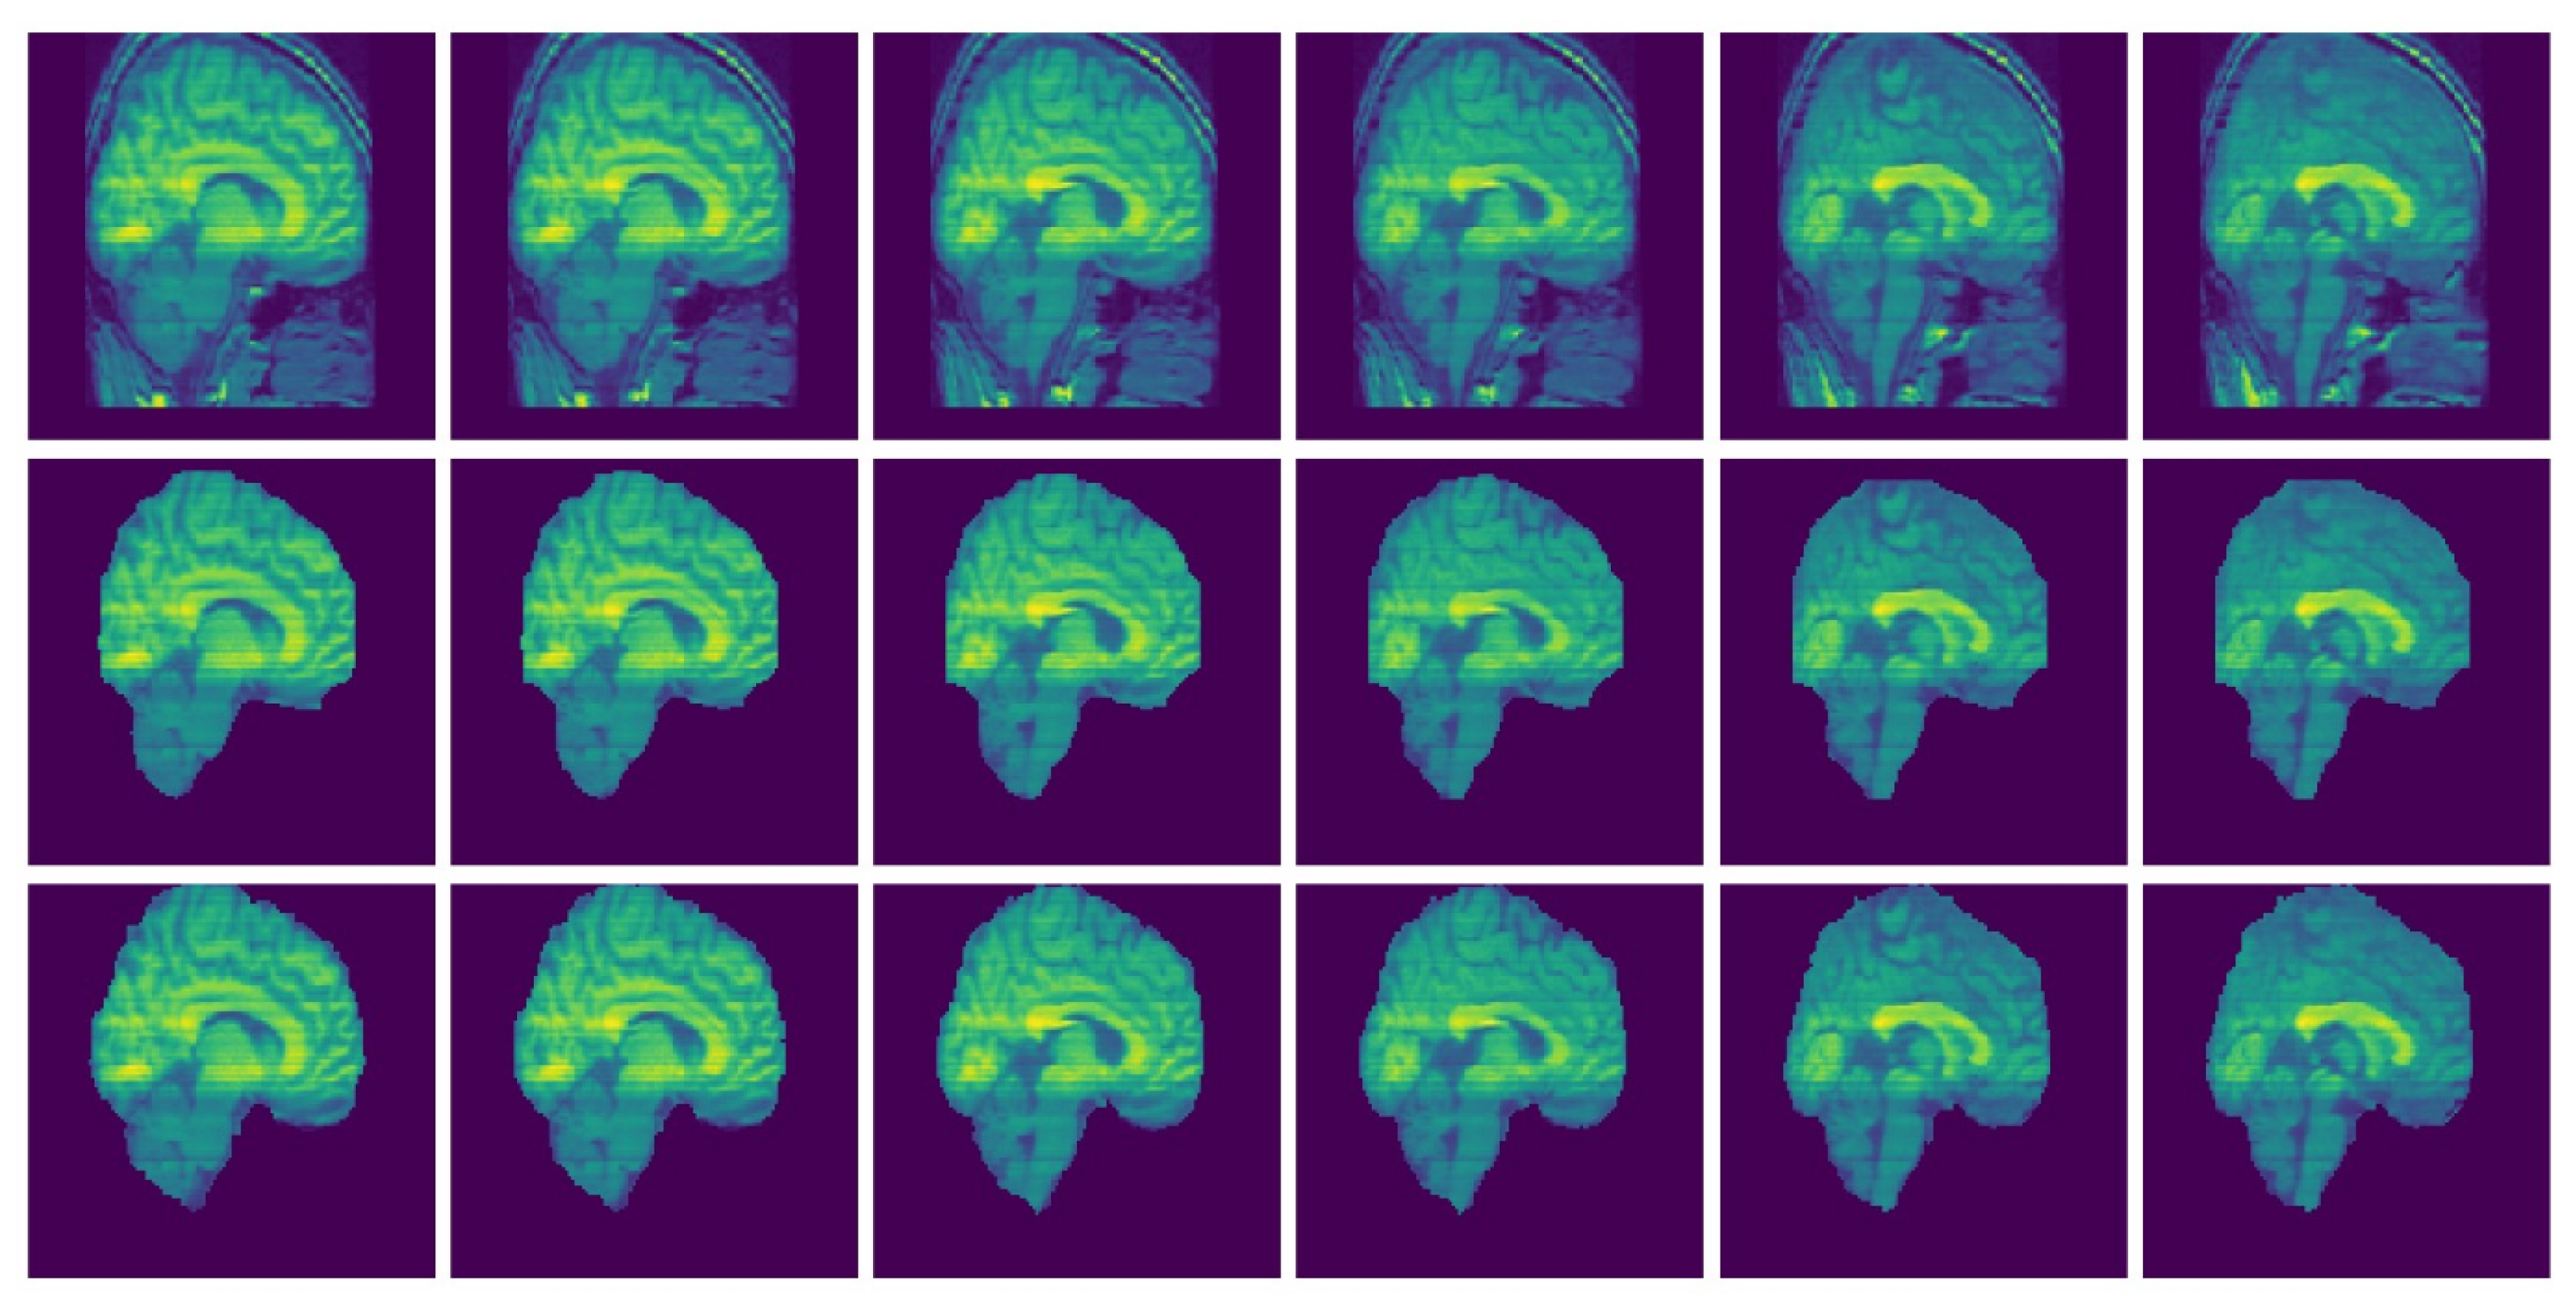

Consistency Analysis of the GUBS across Different Data Sets